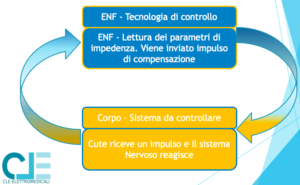

- invia l’impulso

- il sistema analizza la risposta della cellula allo stimolo

- il generatore modifica le caratteristiche di ampiezza, frequenza, larghezza di impulso, del segnale successivo

Con il sistema Elettro-Neuro Feedback ENF, i processi descritti sono ottimizzati perchè il sistema retroazionato registra la risposta del tessuto agli stimoli, attraverso la trasposizione in superficie di una variazione di impedenza dettato dallo stimolo elettrico alla cellula, facendo sì che il generatore elettrico adegui il segnale di stimolo istante per istante.

Oltre all’aspetto terapeutico, il sistema retroazionato ti permette anche di individuare il punto preciso di trattamento, ovvero dove il tessuto necessita di energia perchè squilibtrato.